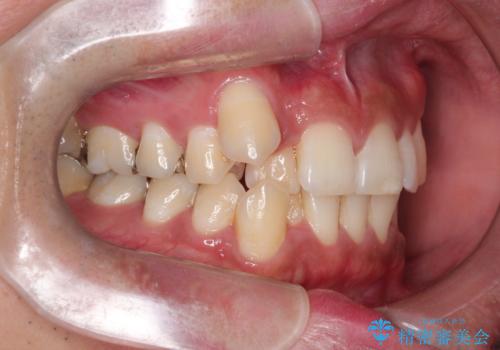

【ワイヤー矯正】八重歯と下の歯の凸凹を治したい

- 主訴:右上の八重歯と、下の歯の凸凹を治したい

上顎右側第一小臼歯と下顎右側第一小臼歯を抜歯しワイヤー矯正を行いました。

右側2級、左側1関係だったため、右側上下第一小臼歯を抜歯し、ワイヤー矯正を行いました。

期間:2年6カ月